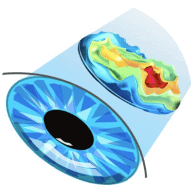

Ajută la îmbunătățirea clarității și luminozității vederii

După primul curs de administrare a Viziton, veți putea distinge mai bine culorile, veți vedea contururile obiectelor mai clar, veți citi literele mici și ochii nu se vor sătura de munca îndelungată la computer.